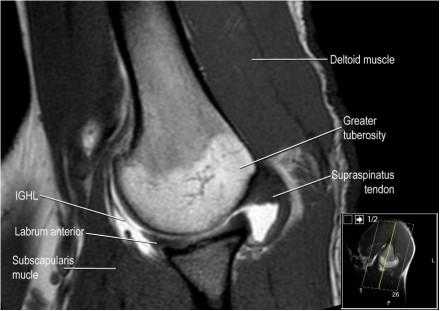

Изображение передних отделов плечевого сустава.

Сухожилие подлопаточной мышцы прикрепляется как к малому бугорку, так и к большому бугорку, давая поддержку длинной головке двуглавой мышцы в борозде двуглавой мышцы. Вывих длинной головки двуглавой мышцы плеча неизбежно приведет к разрыву части подлопаточной сухожилия. Манжета вращателей плеча состоит из сухожилий подлопаточной, надостной, подостная и малой круглой мышц.